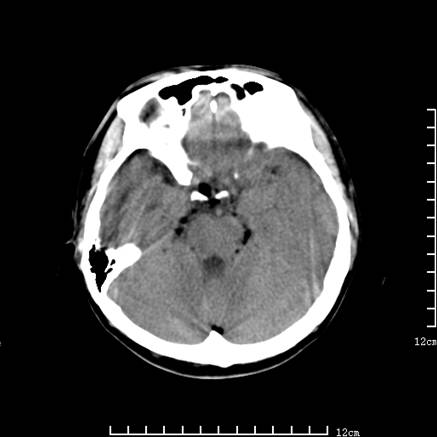

以下是引用jiajie在2008-9-5 22:25:00的发言:[br]男,22岁,头痛1月余。脑室、脑池内病变ct值约-120hu。[br][br]双侧侧脑室内低密度影充填,出现脑脊液脂肪平面,脑池内亦可见弥散分布的斑点状低密度影,脑室脑池未见明显扩大。[br]考虑胆脂瘤破裂后内容物进入脑脊液。